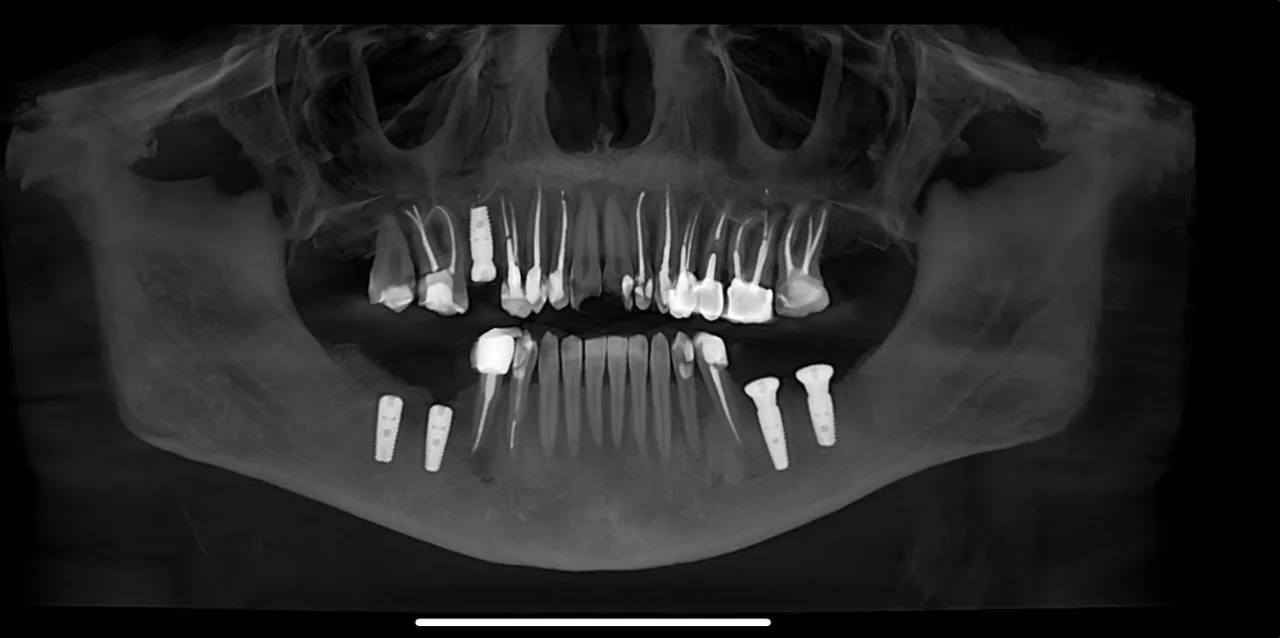

Dual Arch Rehabilitation — All-on-4 & All-on-6

Complete upper and lower jaw rehabilitation. All-on-4 concept for maxilla and All-on-6 for mandible with custom surgical guides.